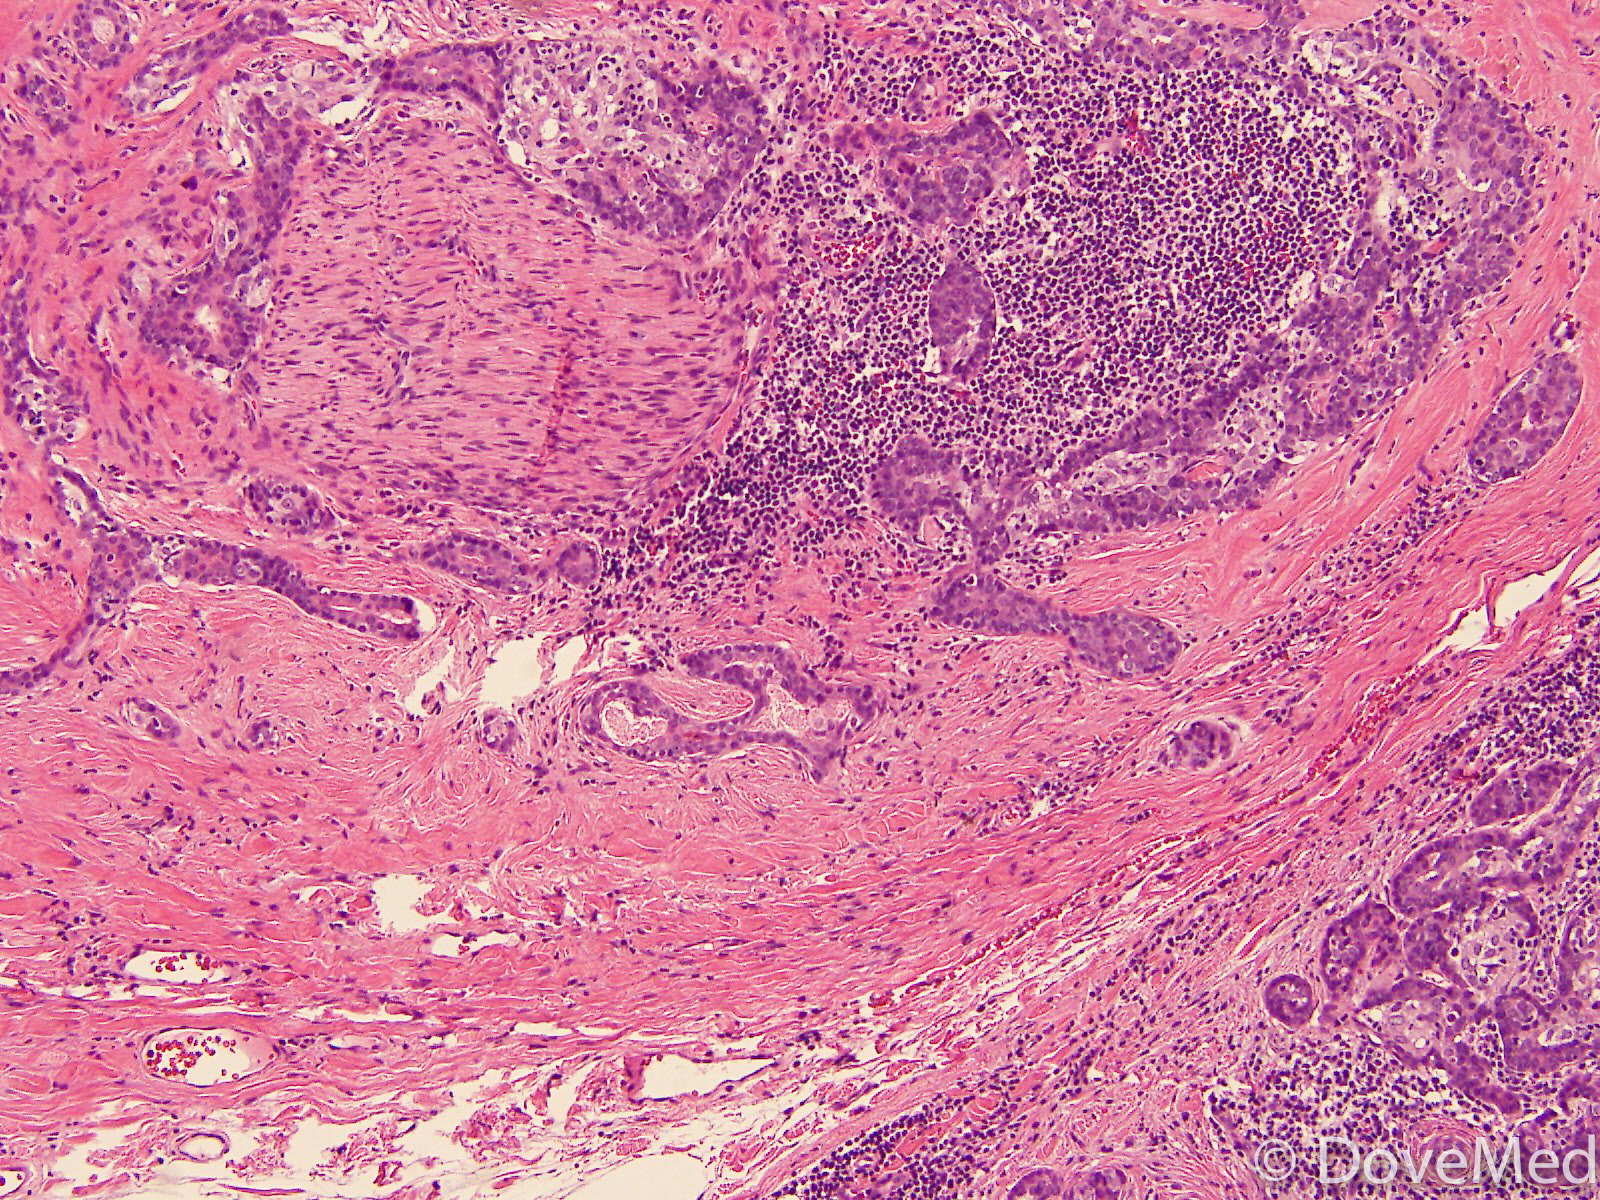

From www.dovemed.com

Adenoid Cystic Carcinoma Adenoid Cystic Eccrine Carcinoma Of Skin in contrast with benign syringomas, syringoid eccrine carcinoma (fig 3c 3c)) exhibits cytonuclear atypia,. cutaneous adnexal tumors are a large group of benign and malignant neoplasms that exhibit morphologic. among appendageal skin tumors, it includes four groups of cutaneous adnexal malignancies (apocrine/eccrine. squamoid eccrine ductal carcinoma (sedc), also known as adenosquamous carcinoma of the skin, is.. Adenoid Cystic Eccrine Carcinoma Of Skin.

Adenoid Cystic Carcinoma of Nasal Cavity Adenoid Cystic Eccrine Carcinoma Of Skin primary cutaneous adenoid cystic carcinoma (pcacc) is a rare adnexal tumor with different histopathologic. in contrast with benign syringomas, syringoid eccrine carcinoma (fig 3c 3c)) exhibits cytonuclear atypia,. among appendageal skin tumors, it includes four groups of cutaneous adnexal malignancies (apocrine/eccrine. eccrine carcinoma (ec) is a rare carcinoma that originates from the eccrine sweat glands of. Adenoid Cystic Eccrine Carcinoma Of Skin.

Adenoid Cystic Carcinoma of External Auditory Canal Adenoid Cystic Eccrine Carcinoma Of Skin squamoid eccrine ductal carcinoma (sedc), also known as adenosquamous carcinoma of the skin, is. cutaneous adnexal tumors are a large group of benign and malignant neoplasms that exhibit morphologic. among appendageal skin tumors, it includes four groups of cutaneous adnexal malignancies (apocrine/eccrine. primary cutaneous adenoid cystic carcinoma (pcacc) is a rare adnexal tumor with different histopathologic.. Adenoid Cystic Eccrine Carcinoma Of Skin.

Adenoid Cystic Carcinoma of Skin Adenoid Cystic Eccrine Carcinoma Of Skin squamoid eccrine ductal carcinoma (sedc), also known as adenosquamous carcinoma of the skin, is. primary cutaneous adenoid cystic carcinoma (pcacc) is a rare adnexal tumor with different histopathologic. cutaneous adnexal tumors are a large group of benign and malignant neoplasms that exhibit morphologic. among appendageal skin tumors, it includes four groups of cutaneous adnexal malignancies (apocrine/eccrine.. Adenoid Cystic Eccrine Carcinoma Of Skin.